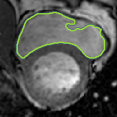

4.2 Visual assessment

We select the case that achieves the highest and lowest dice score for visual assessment. Fig. 4 shows example segmentation results where the proposed method achieved the highest agreement with the ground truth delineations. Fig. 5 shows example segmentation results where the proposed method achieved the lowest agreement with the ground truth delineations.